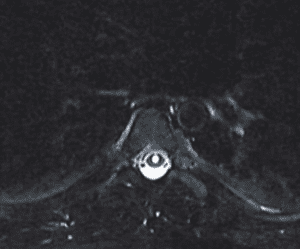

Imaging and other provocative diagnostic test showed the associated problems of Cranial Cervical Instability, incidental thoracic syringomyelia, Hashimoto Thyroidistis, Polycystic Ovarian Syndrome, Nutcracker Syndrome, Postural Orthostatic Hypotension, and Hypo/Hyper intracranial Pressure with spontaneous CSF leaks.

Fig 2. MRI of thoracic spine showing syringomyelia.